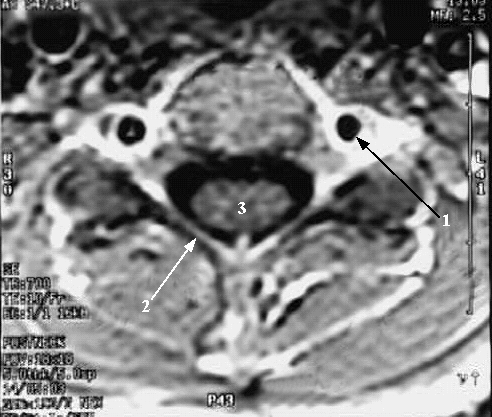

Head & neck: Cervical Spine Cross Zoom:

1. Vertebral artery in Foramen Transversarium

2. Vertebral Lamina

3. Spinal cord